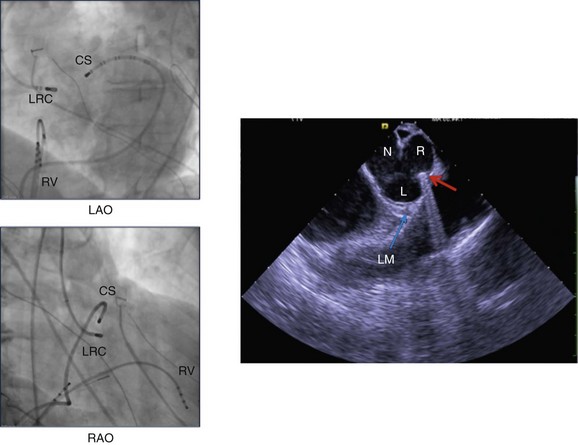

For LVOT mapping catheter localization, unless the operator has experience with aortography for identifying the coronary cusps, ICE is extremely useful for identifying the aortic cusps and the catheter position within the cusps (Figure 81-7). Fluoroscopy alone can often be misleading. The aortic root is typically mapped using the retrograde aortic approach, and it should be mapped as a separate cardiac chamber, with multiple activation points and pace maps taken throughout each coronary cusp at the valve level and up to 2 cm above the valve. The NCC overlies the left atrium and has never been associated with PVC origin in our experience. However, sites throughout the RCC, R/LCC junction, and LCC have been described. In contrast to the RVOT, pace maps in the aortic root are often unreliable because pace mapping can capture distant structures rather than the thin sleeves of myocardium in the aortic root that may be the source of PVCs. The precordial transition will often be a closer match than the RVOT, and although a poor pace map should not dissuade ablation, a perfect pace map is a useful guide for suggesting an aortic root origin.

Figure 81-7 The left panels demonstrate fluoroscopic views of catheter positions in the RAO and LAO projections during an ablation procedure. The coronary sinus catheter (CS) has been advanced distally to the anterior interventricular vein (AIV) for mapping purposes. The ablation catheter is taking a retrograde aortic route to the junction of the right and left coronary cusps (RLC). The exact location of the ablation catheter tip is difficult to confirm using fluoroscopy. In the right panel, a phased-array ICE image is shown, confirming the catheter tip location at the junction of the left (L) and right (R) coronary cusps (red arrow). The location of the left main coronary artery (LM) is also shown (blue arrow). N, Noncoronary cusp.

The primary tool used for mapping in the aortic root is activation mapping. As can be seen with RVOT sites, early sites are typically greater than 20 milliseconds before QRS. In the aortic root, “reversal” of a sharp potential from late during sinus rhythm to early during a PVC confirms the origin as aortic root and often suggests a successful ablation site68 (see Figure 81-5). Because of the proximity of the aortic valve region to the coronary arteries, coronary angiography is recommended before ablation is performed in the aortic root. If ICE is being used by an experienced operator, coronary angiography may be omitted if the site of earliest activation at the R/LCC junction or at the LCC if the coronary artery can be visualized farther than 1 cm away from the left main coronary artery. Registering the electroanatomical map with another imaging modality such as computed tomography (CT) angiography can facilitate identification of the proximal coronary arteries (see Figure 81-5). Visualizing the RCA with ICE is difficult; therefore coronary angiography should be performed before ablation within the right cusp. If ablation at an early site is ineffective, changing the angle of the catheter or looping the catheter into the LV cavity and back up into the aortic root can sometimes help. Mapping in the aortic root should be performed under systemic heparinization, and ablation should be performed with the use of irrigated ablation catheters, because any thrombus can potentially embolize down a coronary artery. Power usually is initiated at 15 to 20 watts and is slowly titrated up to 30 watts. Higher powers usually are not needed, although for an intramyocardial or epicardial focus, powers of up to 50 watts may be used. The impedance drop should be carefully observed and power discontinued at any sign of a rise in impedance.